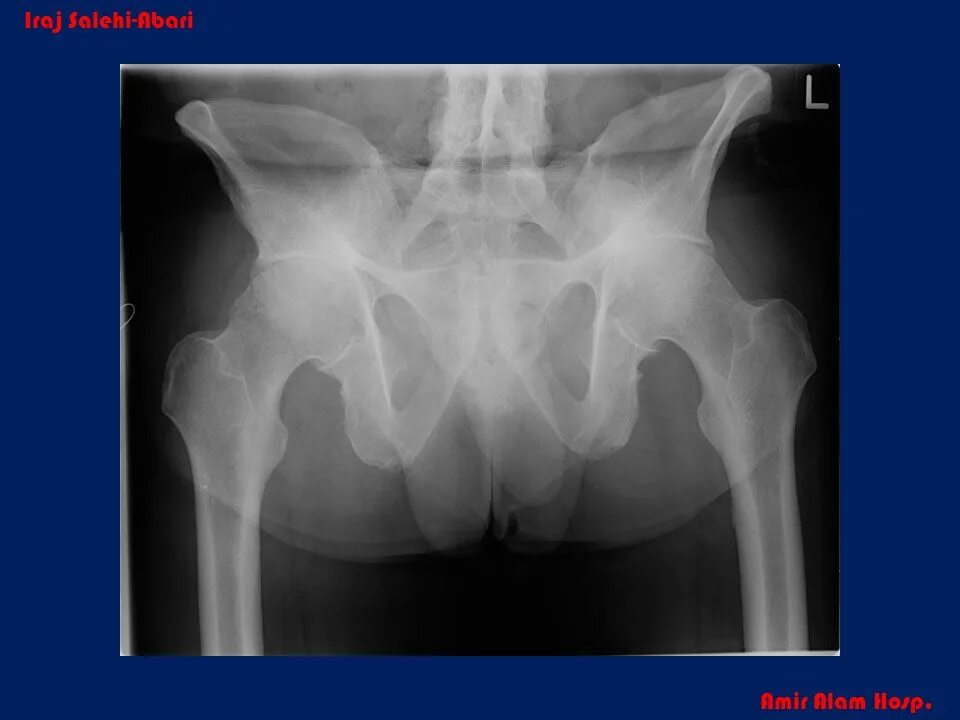

Болезнь бехтерева тазобедренных суставов